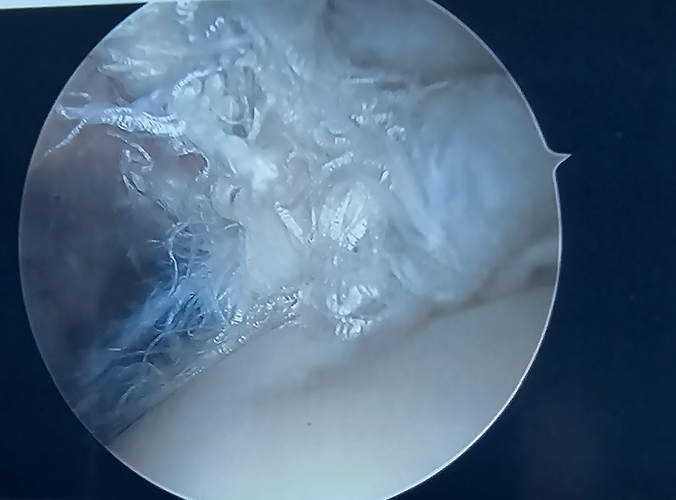

BTW I had William Raasch chief surgeon to the Brewers and Bucks in Milwaukee do my rotator cuff, labrum and surgery in September 2023. I was not to lift until February. I started in November. 1 pound weights. Resitenace bands. I would lock my arm in place and focus on the healthy muscles allowing th ehealing muscles movement and progressive overload. My Bicep tendon should look like a rope, instead it was this mess and impossible to repair.